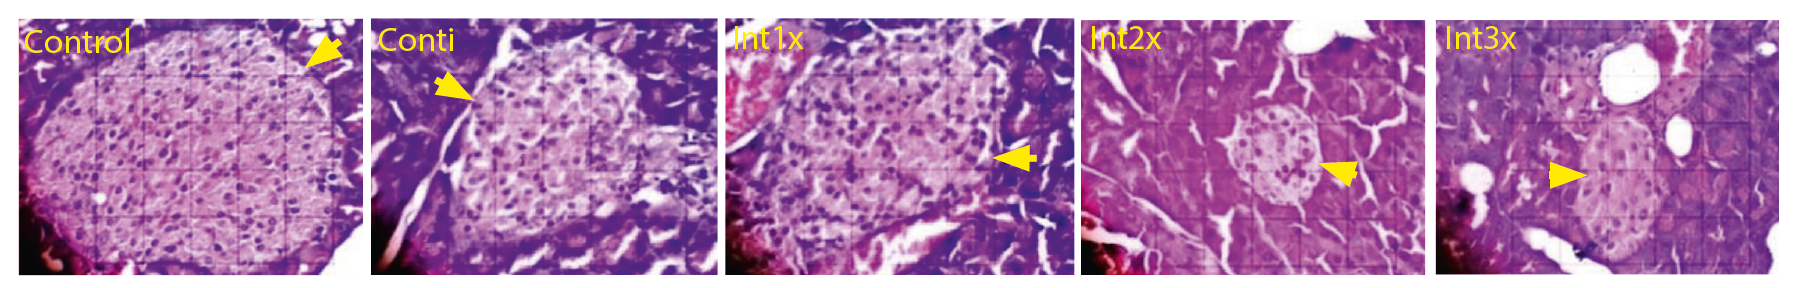

Островки поджелудочной железы

В контрольной группе наблюдались самые крупные островки поджелудочной железы, были обнаружены значительные различия с группами Инт2 и Инт3 (рис. 1 и 2).

Рис. 2. Площадь островков поджелудочной железы (стрелка) при окрашивании гематоксилином и эозином, микроскоп Nikon eclipse Ci, с увеличением 400x, Optilab Viewer 2.2, Image Raster 3.0.